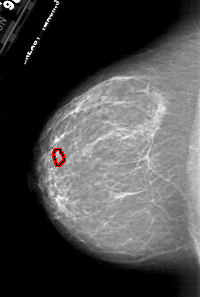

A_1787_1.RIGHT_CC

RIGHT_CC LINES 6871 PIXELS_PER_LINE 4096 BITS_PER_PIXEL 12 RESOLUTION 43.5 NON_OVERLAY

FILE: A_1787_1.LEFT_CC.OVERLAY

TOTAL_ABNORMALITIES 1

ABNORMALITY 1

LESION_TYPE MASS SHAPE LOBULATED MARGINS ILL_DEFINED

ASSESSMENT 4

SUBTLETY 1

PATHOLOGY BENIGN

TOTAL_OUTLINES 1

BOUNDARY